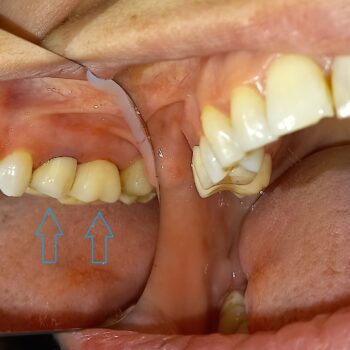

• Αυχενικό σφράγισμα δοντιού